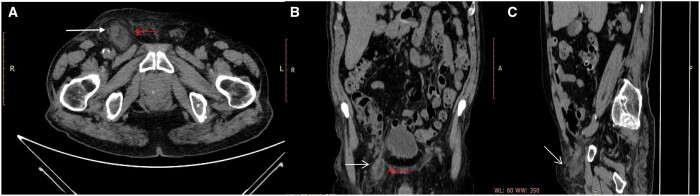

我们报告了一例 "De Garengeot疝"(DGH)病例,这是一种罕见病,当发炎的阑尾位于股疝内时就会发生。阑尾可能涉及炎症或坏死过程,治疗方法是进行紧急手术。它通常是在手术中偶然发现的。股疝发生率为 0.5%-5%。在 0.08%-0.13% 的病例中,由于股骨管颈部狭窄,阑尾可能出现炎症或坏死过程;在这些病例中,需要通过非标准手术程序进行紧急手术。在其他病例中,阑尾炎通常是在手术修补疝气时意外发现的,或者很少在术前通过 CT 诊断出来。因此,我们研究的目的是报告一例 DGH 病例,描述 CT 的主要发现,以改进术前诊断。

We report a case of "De Garengeot's hernia" (DGH), a rare condition that occurs when the inflamed appendix is localized inside a femoral hernia. The appendix may be involved in inflammatory or necrotic processes and the treatment is emergency surgery. It is usually discovered by chance during surgery. It occurs in 0.5%-5% of all femoral hernias. In 0.08%-0.13% of cases, the appendix can present inflammatory or necrotic processes due to the narrowness of the neck of the femoral canal; in these cases, an emergency surgery is required through a no standard surgical procedure. In the other cases, it is usually found accidentally during surgical repair of the hernia or more rarely diagnosed preoperatively by CT. Therefore, the purpose of our study is to report a case of DGH describing CT main findings in order to improve the preoperative diagnosis.